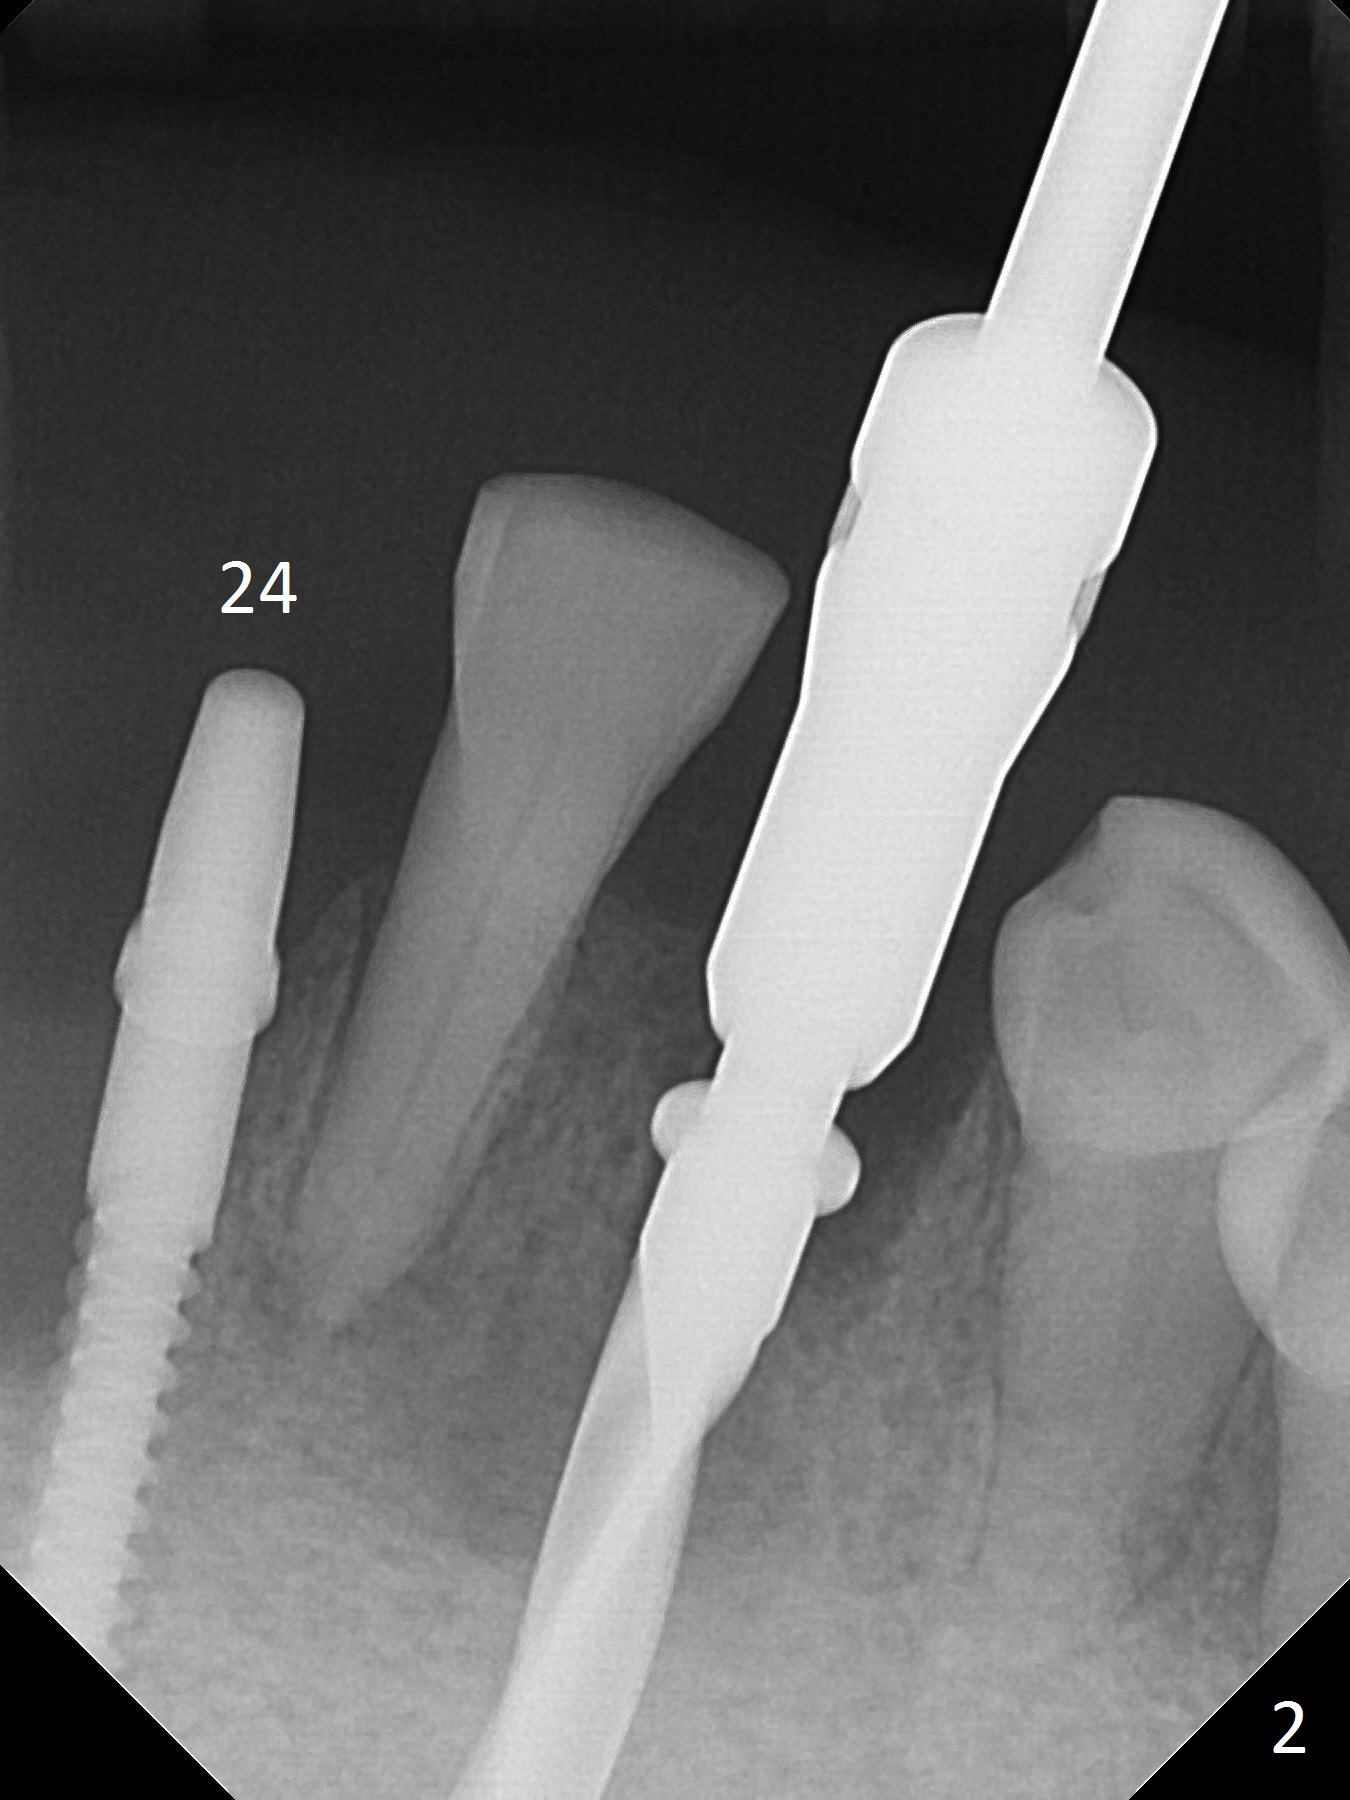

Before surgery, the patient reports that the tooth #25 has inclined to the position of #24 since the latter was extracted (Fig.1). After extraction of the tooth #25, there seems to be more bone vertically at the site of #24 than that of #25. Therefore the osteotomy is initiated at #24. The edentulous space is 9 mm mesiodistally, whereas the incisor width is 6 mm. The first pilot drill is fractured (1.2 mm). The latter is retrieved with incision. With better visibility, the initial osteotomy is found buccal. When a 3x14(2) mm dummy 1-piece implant is being placed partially, the buccal plate seems to be thin. A 2.5x14(4) mm 1-piece implant is placed instead with stability (Fig.2).